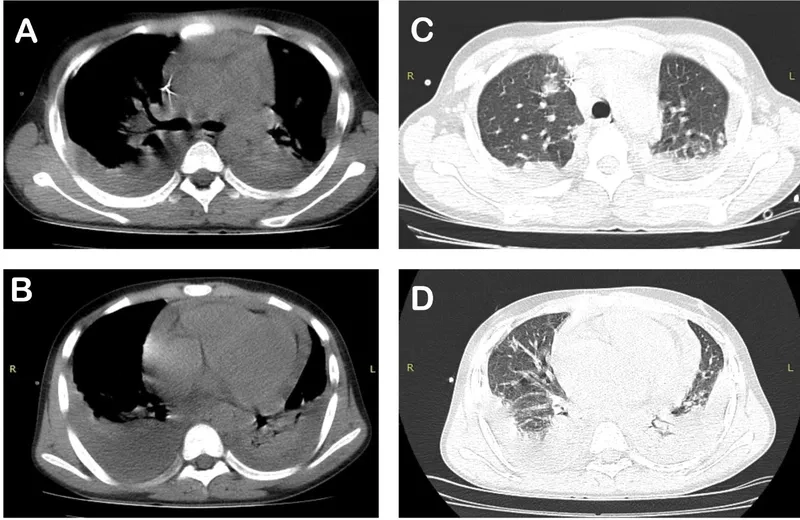

What the symptoms of Glanders look like